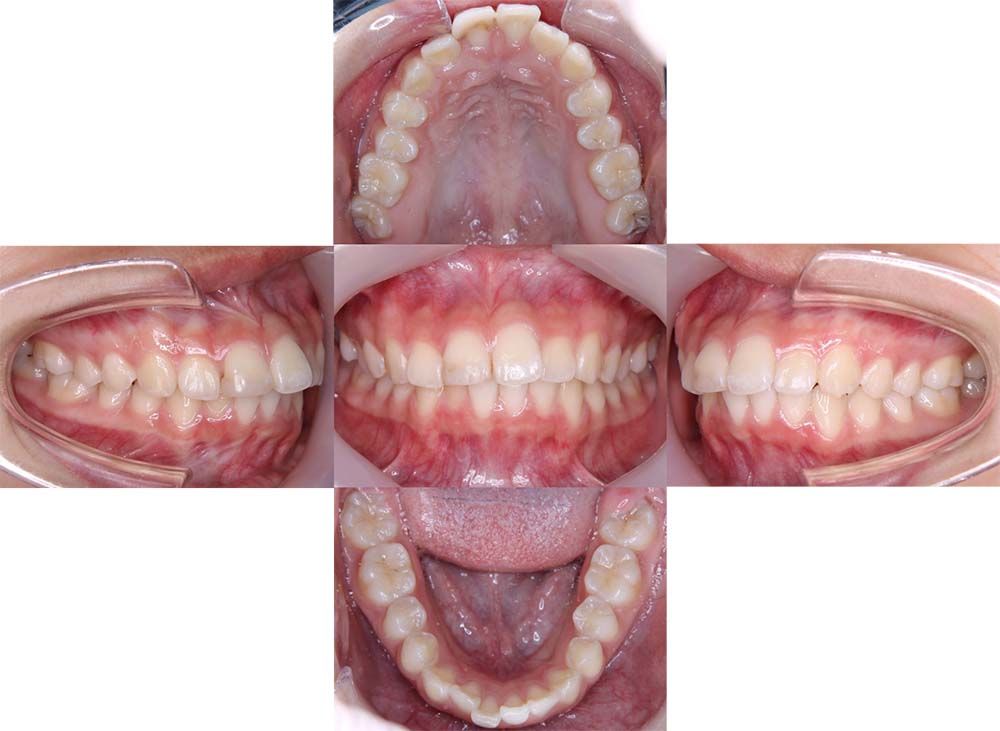

症例04

| 主訴 | 歯並びのガタガタと出っ歯が気になる。 |

| 診断名あるいは主な症状 | 上顎前突、叢生 |

| 年齢/性別 | 16歳・女性 |

| 矯正ステージ | 大人の矯正治療 |

| 治療方法 | ワイヤー矯正 |

| 抜歯部位/抜歯有無 | 抜歯 |

| 治療内容 | 抜歯したスペースを使用し、ガタガタの改善と上下顎前歯を後退させた。 |

| 費用 |

85万円程度(2025.10時点の料金となります。) ※矯正基本料金、審美ブラケットを含む |

| 治療期間 | 2年5ヶ月 |

| 主なリスク・副作用 | 痛み、歯根吸収、歯肉退縮、虫歯、後戻り |